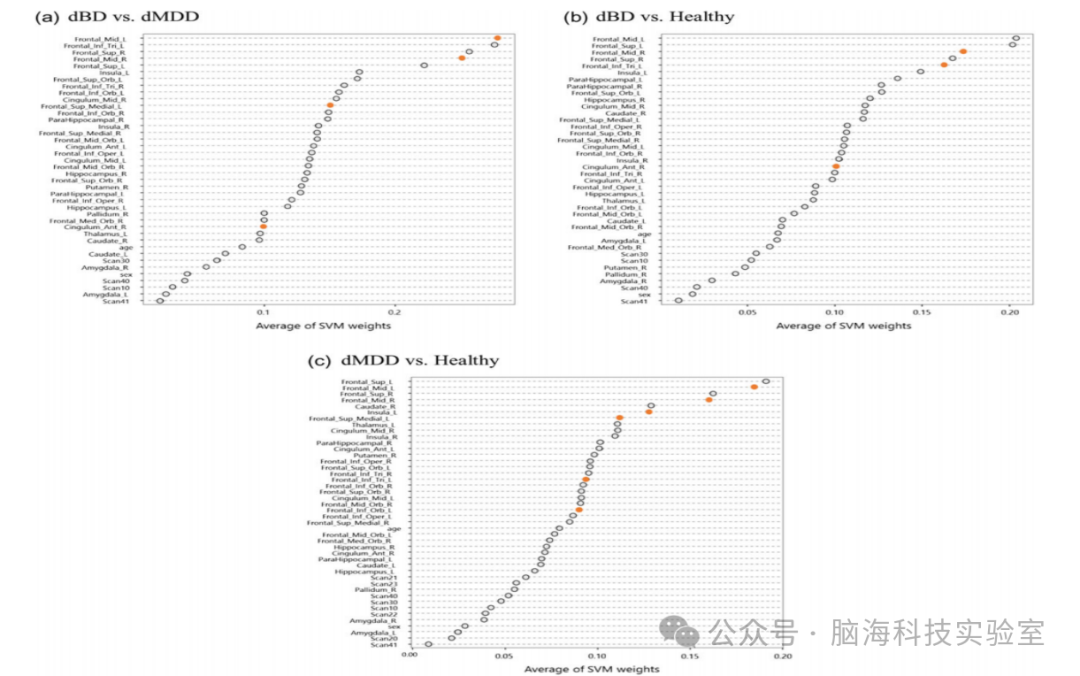

SVM在日本样本中对dBD和dMDD的分类准确率为63.4%,敏感性为69.7%,特异性为46.4%,诊断比值比(DOR)为2.00。双侧中额回、上额回和左侧额下回三角部(这些区域在VBM分析中也显示出显著差异)对分类贡献最大。该分类结果具有统计学意义

dBD患者与健康对照的分类准确率为88.1%,敏感性为92.1%,特异性为73.4%,DOR为32.20。dMDD患者与健康对照的分类准确率为75.9%,敏感性为78.1%,特异性为72.9%,DOR为9.60。

图2:用于跨诊断分类的支持向量机(SVM)权重的区域散点图及其平均值

独立第二队列的VBM和SVM结果部分支持第一队列的结果,尽管对两种障碍的分类准确率低于第一队列。这些较弱的VBM和SVM准确率可能部分解释了第二队列中诊断间前额叶-边缘结构的灰质体积差异较小。第二队列的VBM分析未显示任何区域的灰质体积在诊断间存在显著差异。第二队列的SVM交叉验证分析显示,与第一队列的交叉验证分析相比,诊断分类的准确率显著降低。这些发现表明,第二队列的MRI数据本身在诊断间的分类和区分上存在困难。然而,第一和第二队列的区域SVM权重排名显示出非常相似的模式,表明双侧DLPFC在中额回对分类的贡献强大且可靠。

第四,研究使用训练数据对SVM分析的最优参数C进行了10折交叉验证,使用了5个候选参数。研究可能通过使用网格搜索图方法找到更优的参数。使用的5个典型参数候选在本研究中经过探索性测试后被确认为适当(数据未显示)。研究使用PCA对每个区域进行特征提取,保留了90%的方差,这没有通过交叉验证进行优化。首先通过保留95%的方差进行这种特征提取分析,结果与保留90%方差的原始分析略有不同(数据未显示)。因此,尽管更好的参数优化可能会提高SVM的分类性能,但研究目前的结果仍然是有效的。第五,研究发现美国样本的SVM交叉验证显示出非常低的敏感性(dBD与健康为0.18,dMDD与健康为0.13)。这可能是由于患者与健康受试者之间的样本量严重不平衡(36例dBD、43例dMDD与132例健康受试者)。未来需要在美国样本中进行三组诊断数量相当的研究,以进一步验证结果。最后,平均SVM权重的结果表明,日本和美国的结果之间显示出相似的分布(图4)。似乎较大的权重简单地出现在较大的区域中,但事实可能并非如此简单。由于SVM分析使用了从VBM分析中获得的体素信号强度,一个区域中的较大权重意味着更大的平均体素信号和更多的体素数量。例如,它可能表明左右两侧的ROI(应该包含相似数量的体素)位于不同的位置(补充表5)。因此,尽管较大的区域倾向于显示出较大的权重,但在解释图4的结果时,应考虑每个体素的信号强度。